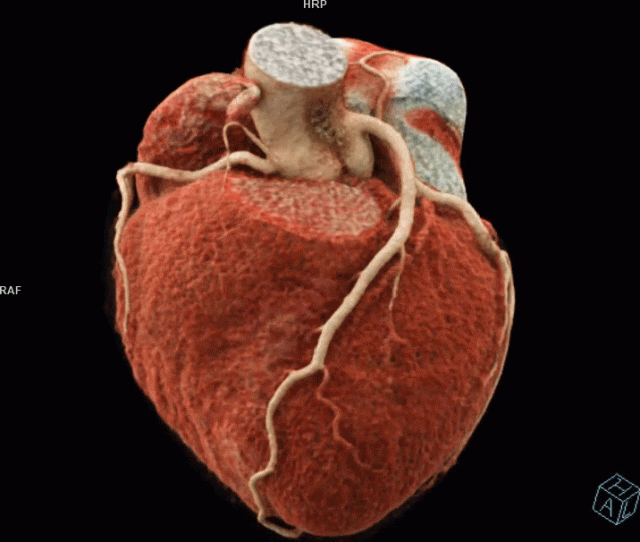

- Cardiac Functional, Multichamber Analysis and 3D Visualization

Cardiac Function

3D Cardiac Rotation

Cinematic Rendering of the Heart